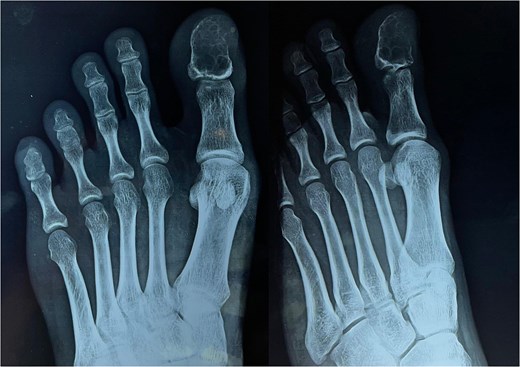

The skin and nails surrounding the growth are normal. It was linked to pressure-related discomfort. There was no history of trauma in the past. There was no fever or presence of any other comorbidity. A systematic assessment revealed no anomalies. Tests for renal function, plasma glucose, complete blood count, and other standard laboratory procedures were all within normal ranges. A radiographic examination reveals a coarse trabeculation and an osteolytic lesion in the great toe’s distal phalanx, which may indicate a benign bone malignancy (Fig. 2).